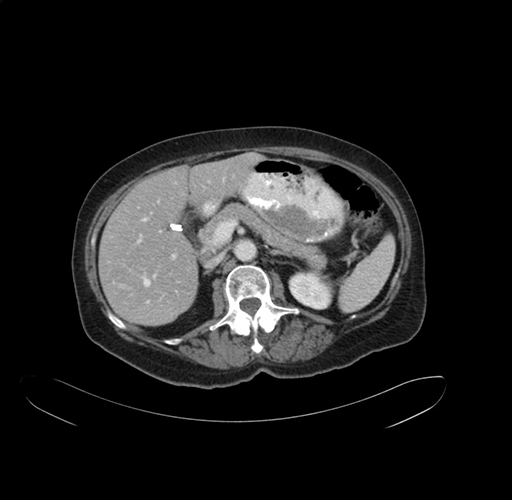

Pre-Chemo: Coronal Venous